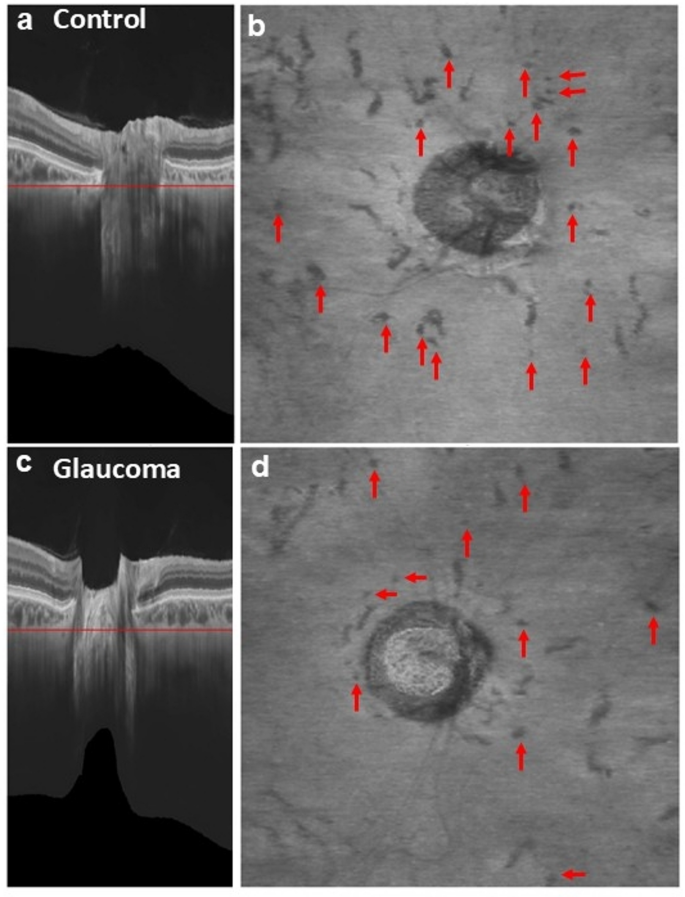

Representative images of eyes with glaucoma and healthy eyes are shown in Fig. 1 and in Supplementary Videos 1 and 2, respectively. The number of PPSVs was significantly lower in the overall glaucoma group than in the control group (P < 0.001). We also analyzed a subgroup of glaucoma patients whose ages were within ± 3 years of the mean age of the control group. The number of PPSVs was significantly lower in the young glaucoma group than in the control group (mean [SD], 18.3 [3.6] vs. 26.6 [4.3]; P < 0.001) (Fig. 2). The ROC curve had an area under the curve (AUC) of 0.95 (95% confidence interval, 0.93–0.97), and the sensitivity and specificity for identifying glaucoma at a cutoff value of 21.50 were 84.6% and 91.7%, respectively. A representative case of a 49-year-old man with preperimetric glaucoma is shown in Fig. 3. The fundus photograph shows enlargement of the optic cup without RNFL defects (Fig. 3a), or visual field defects (Fig. 3b). However, OCT revealed superotemporal thinning of the RNFL (Fig. 3c). This case was independent of the study dataset. However, the patient had a reduced number of PPSVs of 21.50 (Fig. 3d and e) and is being followed-up for the potential development of glaucoma in the future.

Representative OCT images from a control participant (a, b) and a patient with glaucoma (c, d). (a) and (c) show OCT-B scans with deep-learning-based enhancement. The red lines indicate the levels of the en-face OCT images created in (b) and (d), respectively. (b) and (d) show en-face OCT images generated from the enhanced OCT B-scans. Each hyporeflective spot (red arrow) was regarded as a vessel when it was continuous in the surrounding levels of the en-face OCT images. OCT, optical coherence tomography.